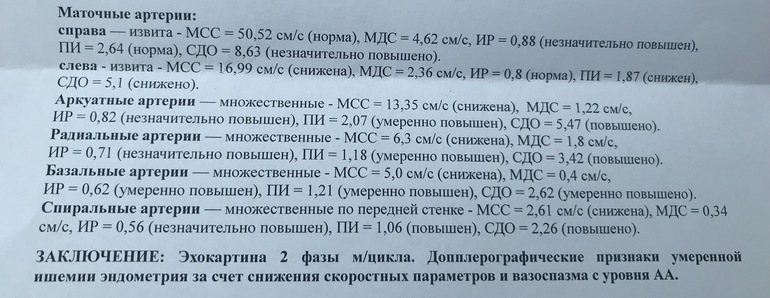

Кто понимает в кровотоке, гляньте